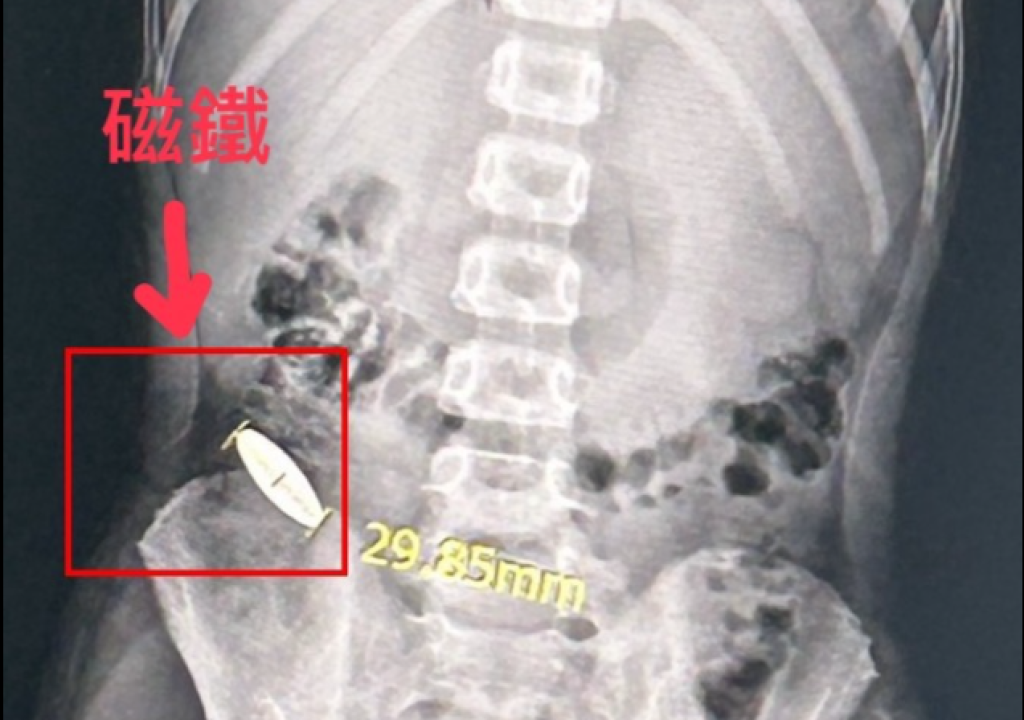

台南安南區某安親班傳霸凌!6歲童被11歲童逼吞3公分磁鐵 驚悚X光照片曝光

台南安南區某安親班傳霸凌,6歲孩子被11歲學長強迫吞下約3公分磁鐵。對此,教育局指出,針對吞食磁鐵異物的學生,學校將持續進行關懷並提供後續輔導措施。-